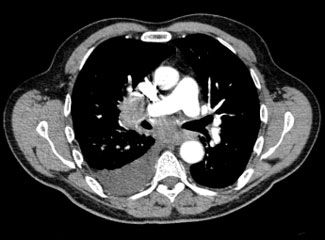

The patient was admitted with the diagnosis of right lower lobe (RLL) pneumonia on the basis of RLL consolidation on his radiograph. He was treated with intravenous ceftriaxone and azithromycin. However, there was no improvement in his symptoms despite treatment with the antibiotics; therefore, a CT scan of the chest was obtained. It revealed emphysema and mediastinal lymphadenopathy in the pretracheal and subcarinal locations (Figure 1). A moderate right-sided pleural effusion and multiple nodular opacities (measuring less than 1 cm) in right middle and lower lobes with septal thickening were noted, suggesting a lymphangitic tumor (Figure 2).